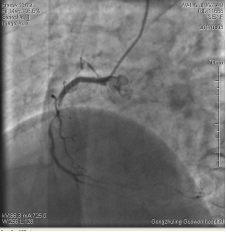

3月3日14時30分:經(jīng)右橈動脈行冠脈造影見:左主干未見明顯異常,TIMI血流3級,前降支開口正常,近中段20%狹窄,TIMI血流3級;回旋支開口正常,中遠段75%狹窄,TIMI血流3級。右冠狀動脈開口正常,中段長病變,最重99%狹窄, TIMI血流3級。

圖1 回旋支遠段70%狹窄 圖2 右冠脈中段99%狹窄